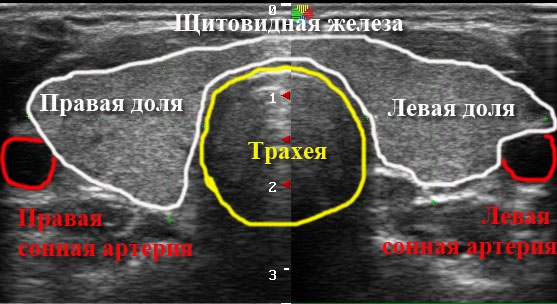

Скрининг рака щитовидной железы: Новые УЗИ-критерии и что они означают для пациента Когда речь заходит о здоровье щитовидной железы, важнейшую роль играют

Диагностика рака щитовидной железы: как ультразвук помогает в раннем выявлении Рак щитовидной железы — это одна из наиболее часто встречающихся онкологических